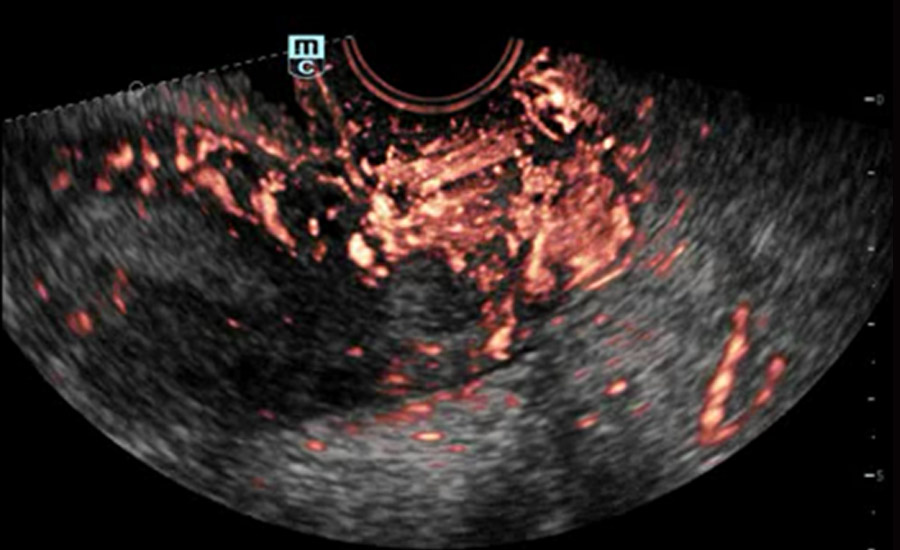

UMA (Ultra-Micro Angiography)

The innovative technology breaks the bottlenecks of traditional Doppler imaging. With ultra-high spatial resolution and flow sensitivity, it allows detecting super-subtle and super-slow flow perfusions, thereby extending the clinical application of qualitative and quantitative ultrasound evaluation in fetal brain, kidney, placenta, endometrium, ovary, etc.

UMA - uterine and endometrial flow